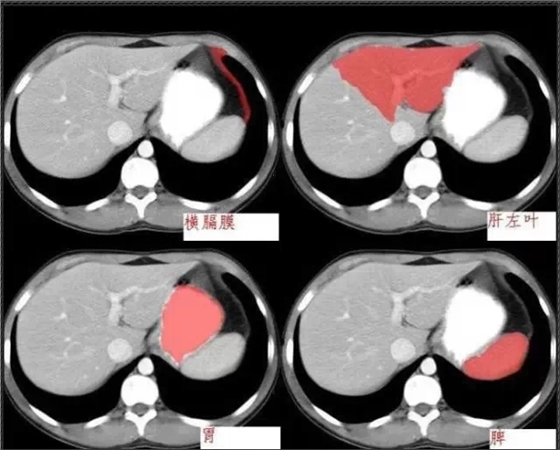

640.webp (4).jpg

640.webp (5).jpg

640.webp (6).jpg

640.jpg